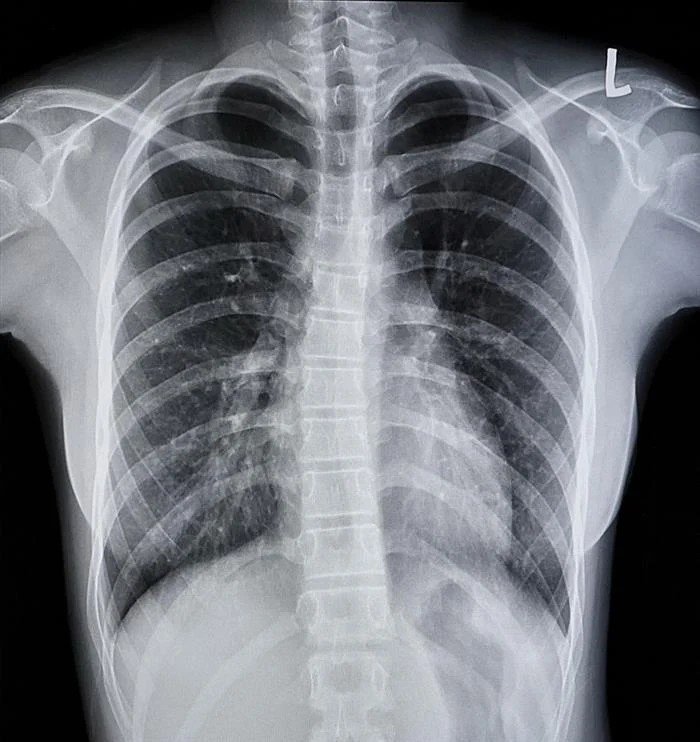

По прегледот и снимањето, на десното белодробно крило биле пронајдени „сомнителни сенки“, а последователната бронхоскопија покажала дека боледува од инфекција предизвикана од габата Aspergillus.